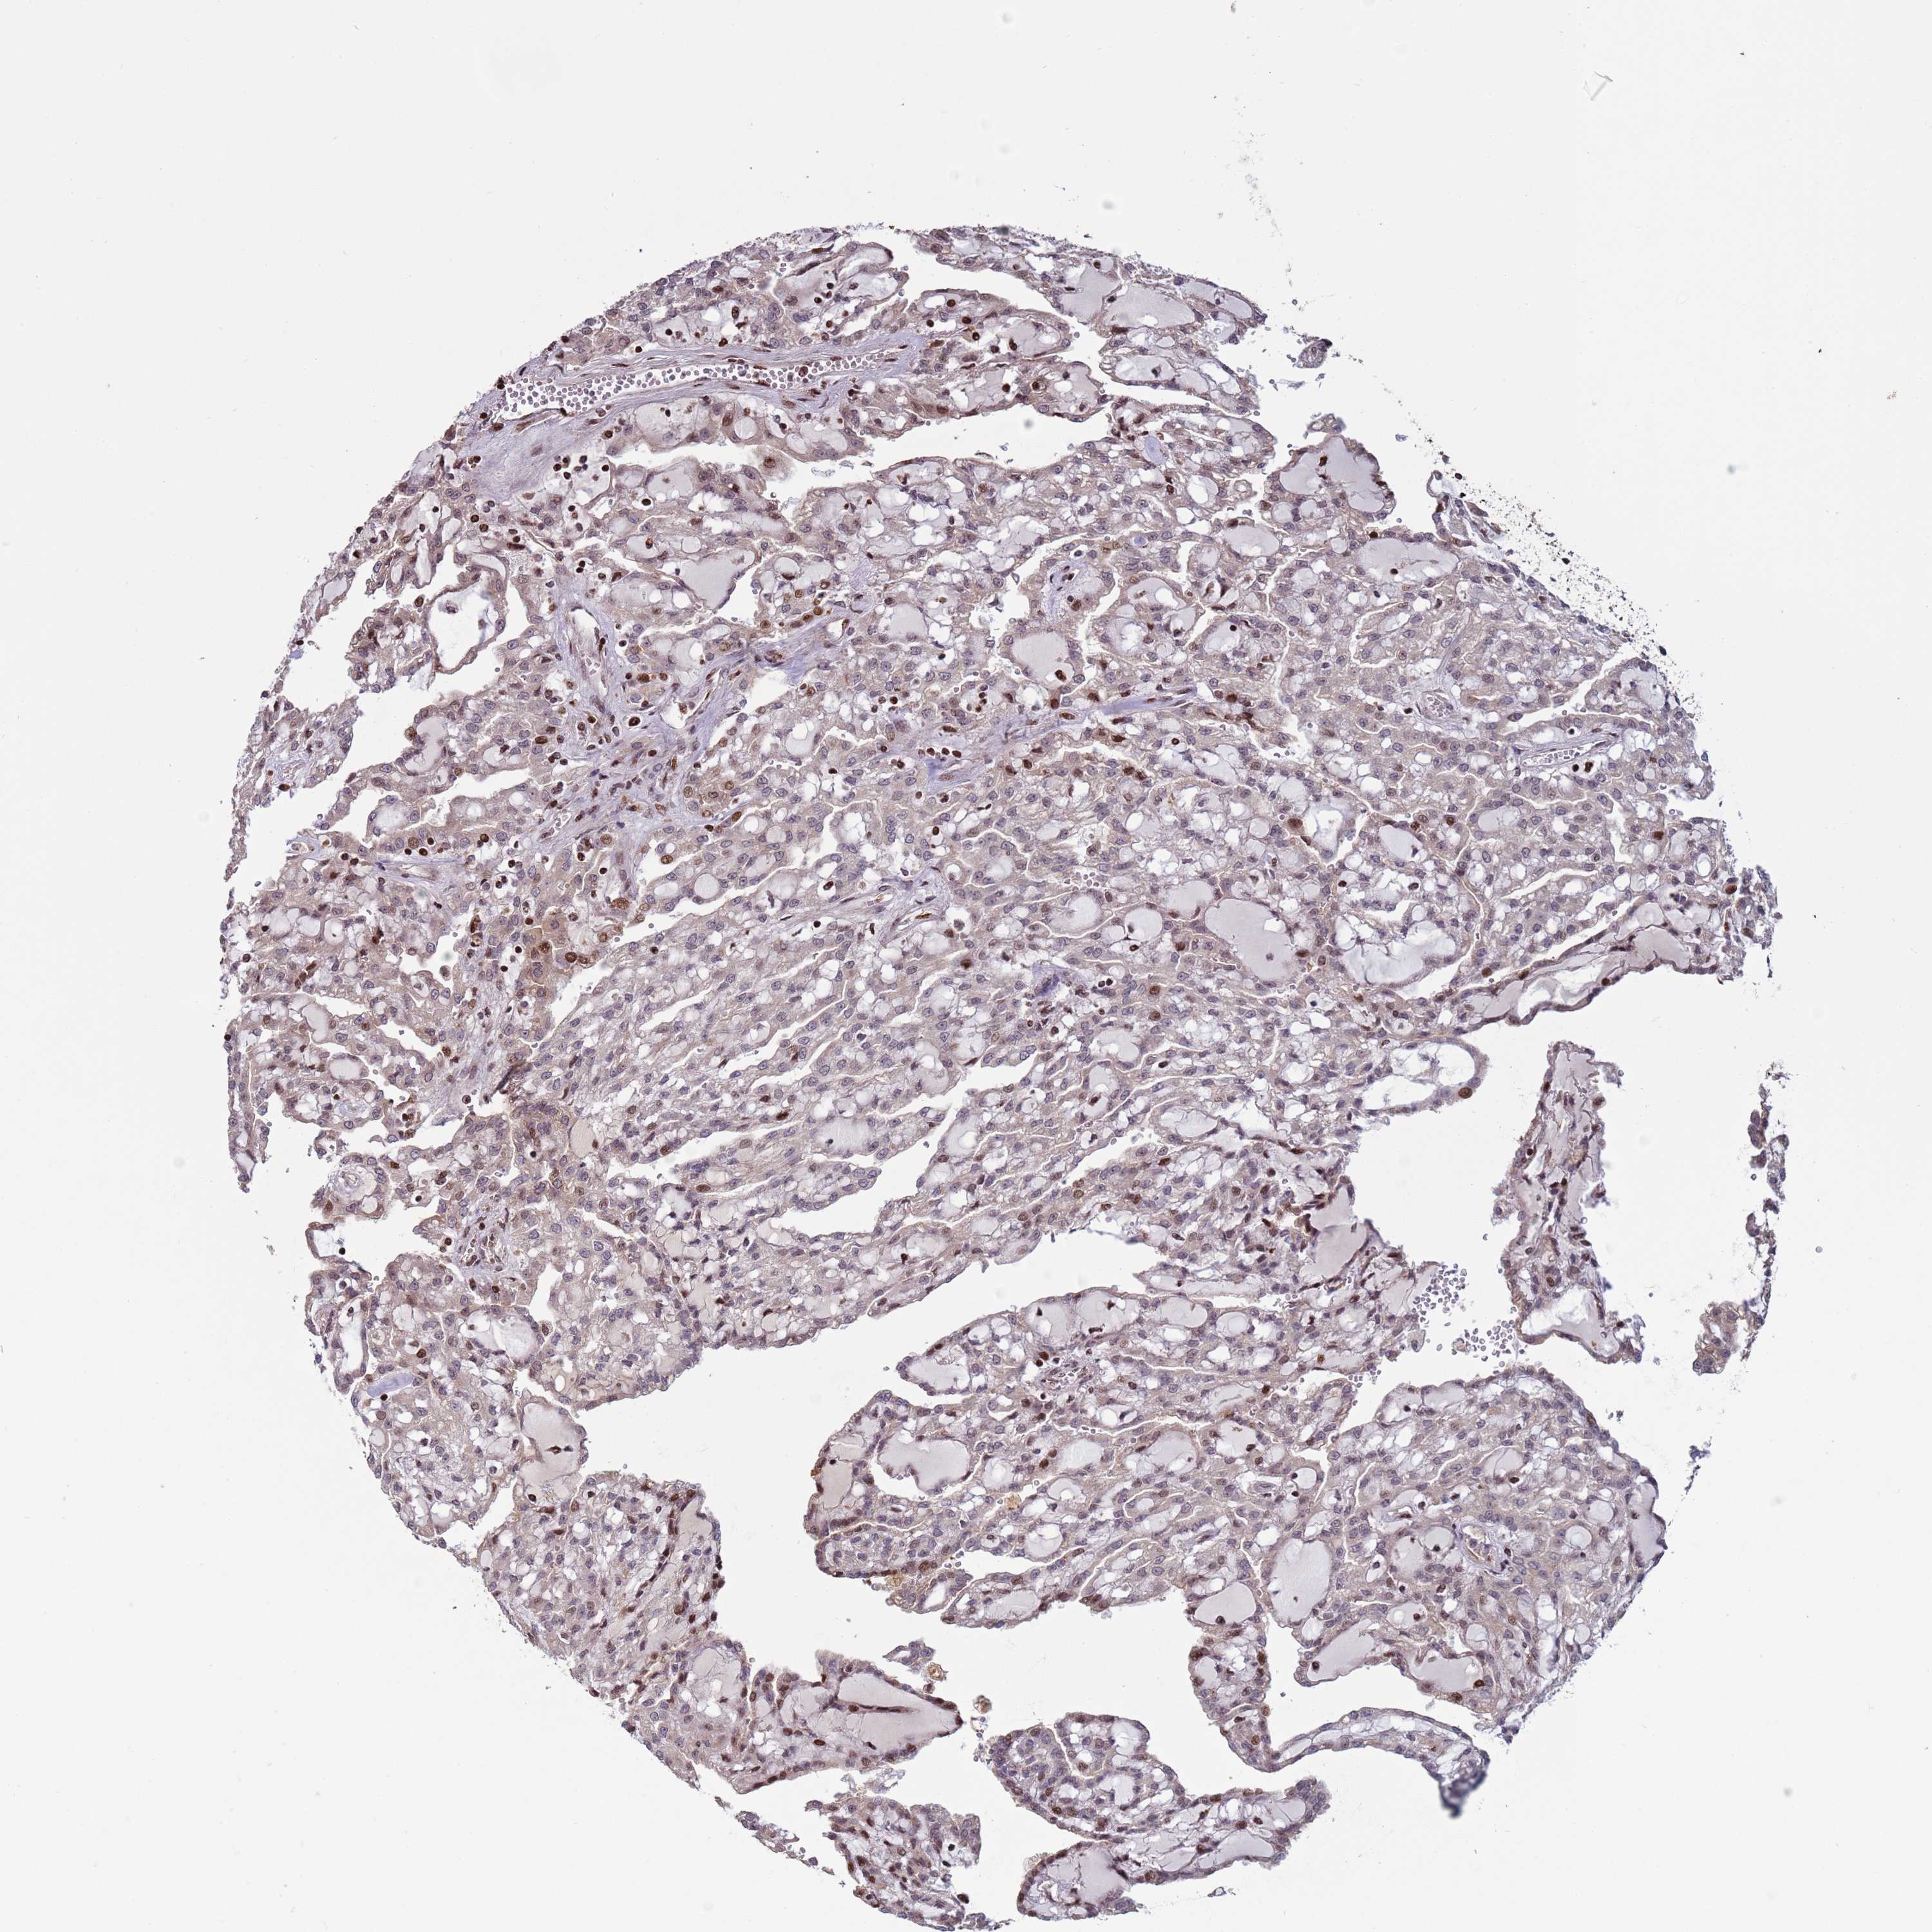

KIDNEY RENAL CLEAR CELL CARCINOMA (VALIDATION) - Interactive survival scatter ploti

The Survival Scatter plot shows the clinical status (i.e. dead or alive) for all individuals in the patient cohort, based on the same data that underlies the corresponding Kaplan-Meier plots. Patients that are alive at last time for follow-up are shown in blue and patients who have died during the study are shown in red.

The x-axis shows the expression levels (FPKM) of the investigated gene in the tumor tissue at the time of diagnosis. The y-axis shows the follow-up time after diagnosis (years). Both axes are complimented with kernel density curves demonstrating the data density over the axes. The top density plot shows the expression levels (FPKM) distribution among dead (red) and alive patients (blue). The right density plot shows the data density of the survived years of dead patients with high and low expression levels respectively, stratified using the cutoff indicated by the vertical dashed line through the Survival Scatter plot. This cutoff is automatically defined based on the FPKM cutoff that minimizes the p-score. The cutoff can be changed by dragging the vertical line or by entering a cutoff value in the square labeled "Current cut-off".

Under the Survival Scatter plot the p-score landscape (black curve; left axis) is shown together with dead median separation (red curve; right axis). Dead median separation is the difference in median mRNA expression between patients who have died with high and low expression, respectively. It is calculated as follows: median FPKM expression of dead patients with high expression - median FPKM expression of dead patients with low expression. This is intended to aid the user in visually exploring custom cutoffs and the associated p-scores and dead median separation.

Individual patient data is displayed and can be filtered by clicking on one or more of the category buttons on the top of the page. Categories describing expression level and patient information include: high, low, alive, dead, female, male and tumor stages. The scale of the x-axis can be toggled between linear and log-scale by clicking on the "x log" button. Mouse-over function shows TCGA ID, patient information and mRNA expression (FPKM) for each patient.

& Survival analysisi

Kaplan-Meier plots summarize results from analysis of correlation between mRNA expression level and patient survival. Patients were divided based on level of expression into one of the two groups "low" (under cut off) or "high" (over cut off). X-axis shows time for survival (years) and y-axis shows the probability of survival, where 1.0 corresponds to 100 percent.

HGH1 is not prognostic in Kidney Renal Clear Cell Carcinoma (validation)

Best expression cut offi

Based on the FPKM value of each gene, patients were classified into two groups and association between prognosis (survival) and gene expression (FPKM) was examined. The best expression cut-off refers the FPKM value that yields maximal difference with regard to survival between the two groups at the lowest log-rank P-value. Best expression cut-off was selected based on survival analysis .

When clicking on this number, the vertical dashed line indicating cut-off, the interactive survival plot, and the Kaplan-Meier curve will be adjusted to show results based on the best expression cut-off.

: 7.16

P scorei

Log-rank P value for Kaplan-Meier plot showing results from analysis of correlation between mRNA expression level and patient survival.

N/A

Average pTPM 5.1

Number of samples 100